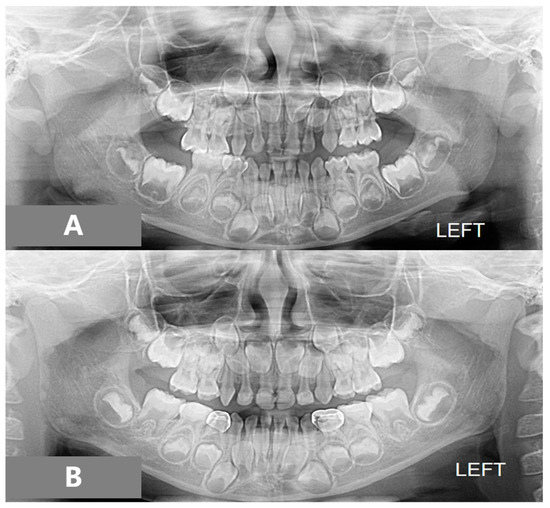

2.2. Assessments

3. Results